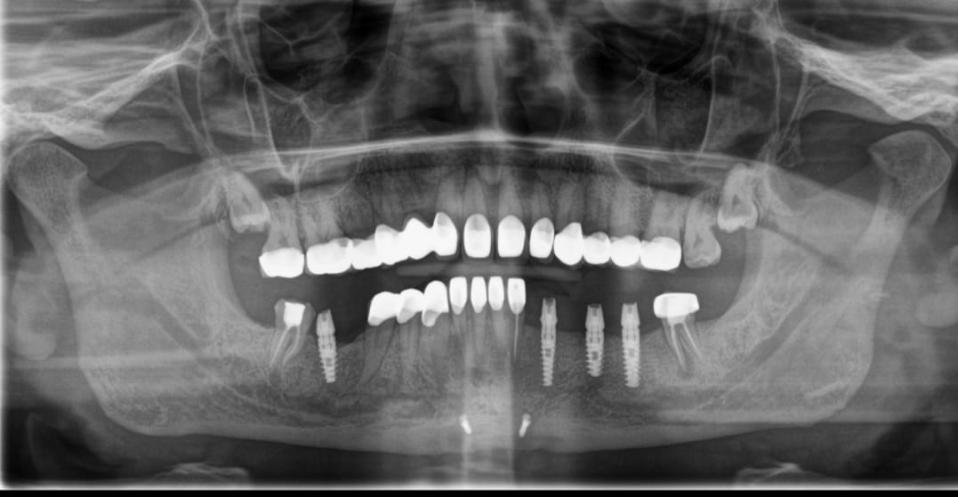

- Initial Consultation: Your oral health would be evaluated clinically along with imaging tests (like dental x-rays and CBCT scans) to determine the best treatment plan and the type of implant to be placed.

- Implant Placement: The implantologist surgically places the titanium post into the jawbone under local/general anesthesia, depending on the number of implants to be placed. A healing period of 3 to 6 months follows to allow for the osseointegration of the implant, which is nothing but the bony fusion of the implant with the jawbone. When comparing dental implants vs bridges, implants provide a more stable and long-lasting solution as they integrate directly with the bone, unlike bridges that rely on adjacent teeth for support.